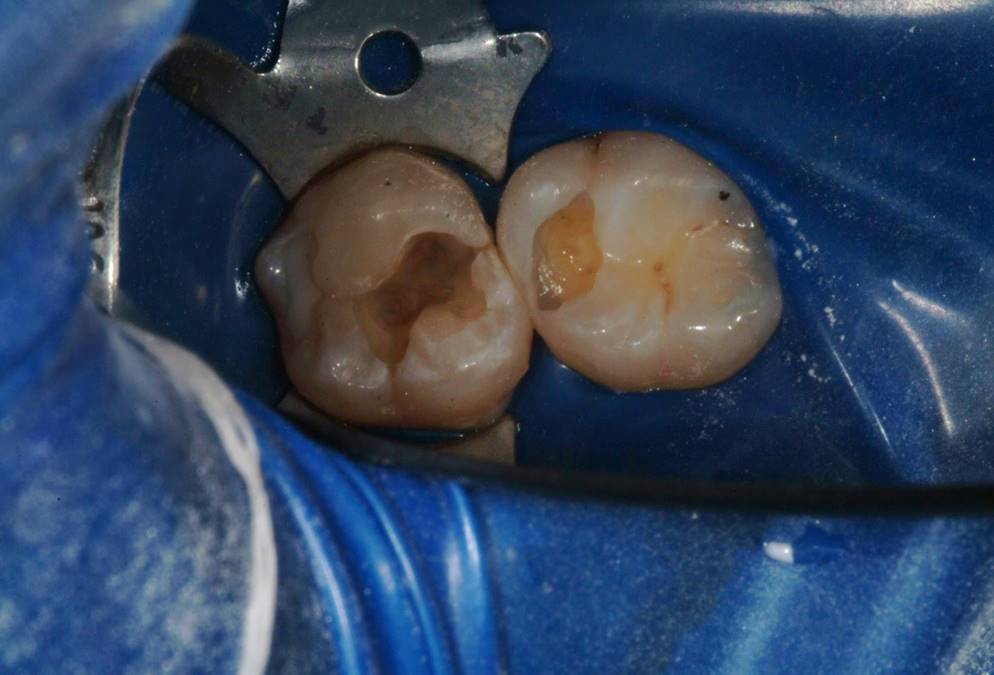

The most common problems associated with direct composite restorations include the time- and labor-intensive nature of the layering techniques involved with their placement, issues surrounding material adaptation, difficulty achieving tight contacts, polymerization and volumetric shrinkage, postoperative sensitivity, and microleakage leading to secondary caries.1,2 Composite layering protocol is dependent on restoration depth. Contributing to the time-intensive and technique-sensitive nature of multiple-layer restorations are the challenges encountered when ensuring that all composite layers combine properly and adapt well to each other and cavity walls, without producing porosities and voids (Figure 1).3

Fig 1. Typically for preparations > 2 mm, numerous layers of composite must be placed into the preparation to diminish polymerization shrinkage and stresses on tooth structure.

Figure 1